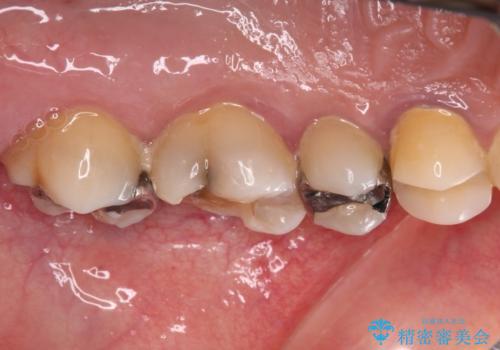

- 奥歯を治療しようと他院で開始したものの、放置してしまったとのことで来院された患者様です。

外れてしまった銀歯や穴の空いた仮歯などあり、適合の悪い被せものと合わせて、セラミッククラウンやセラミックインレーにて治療と行うこととしました。